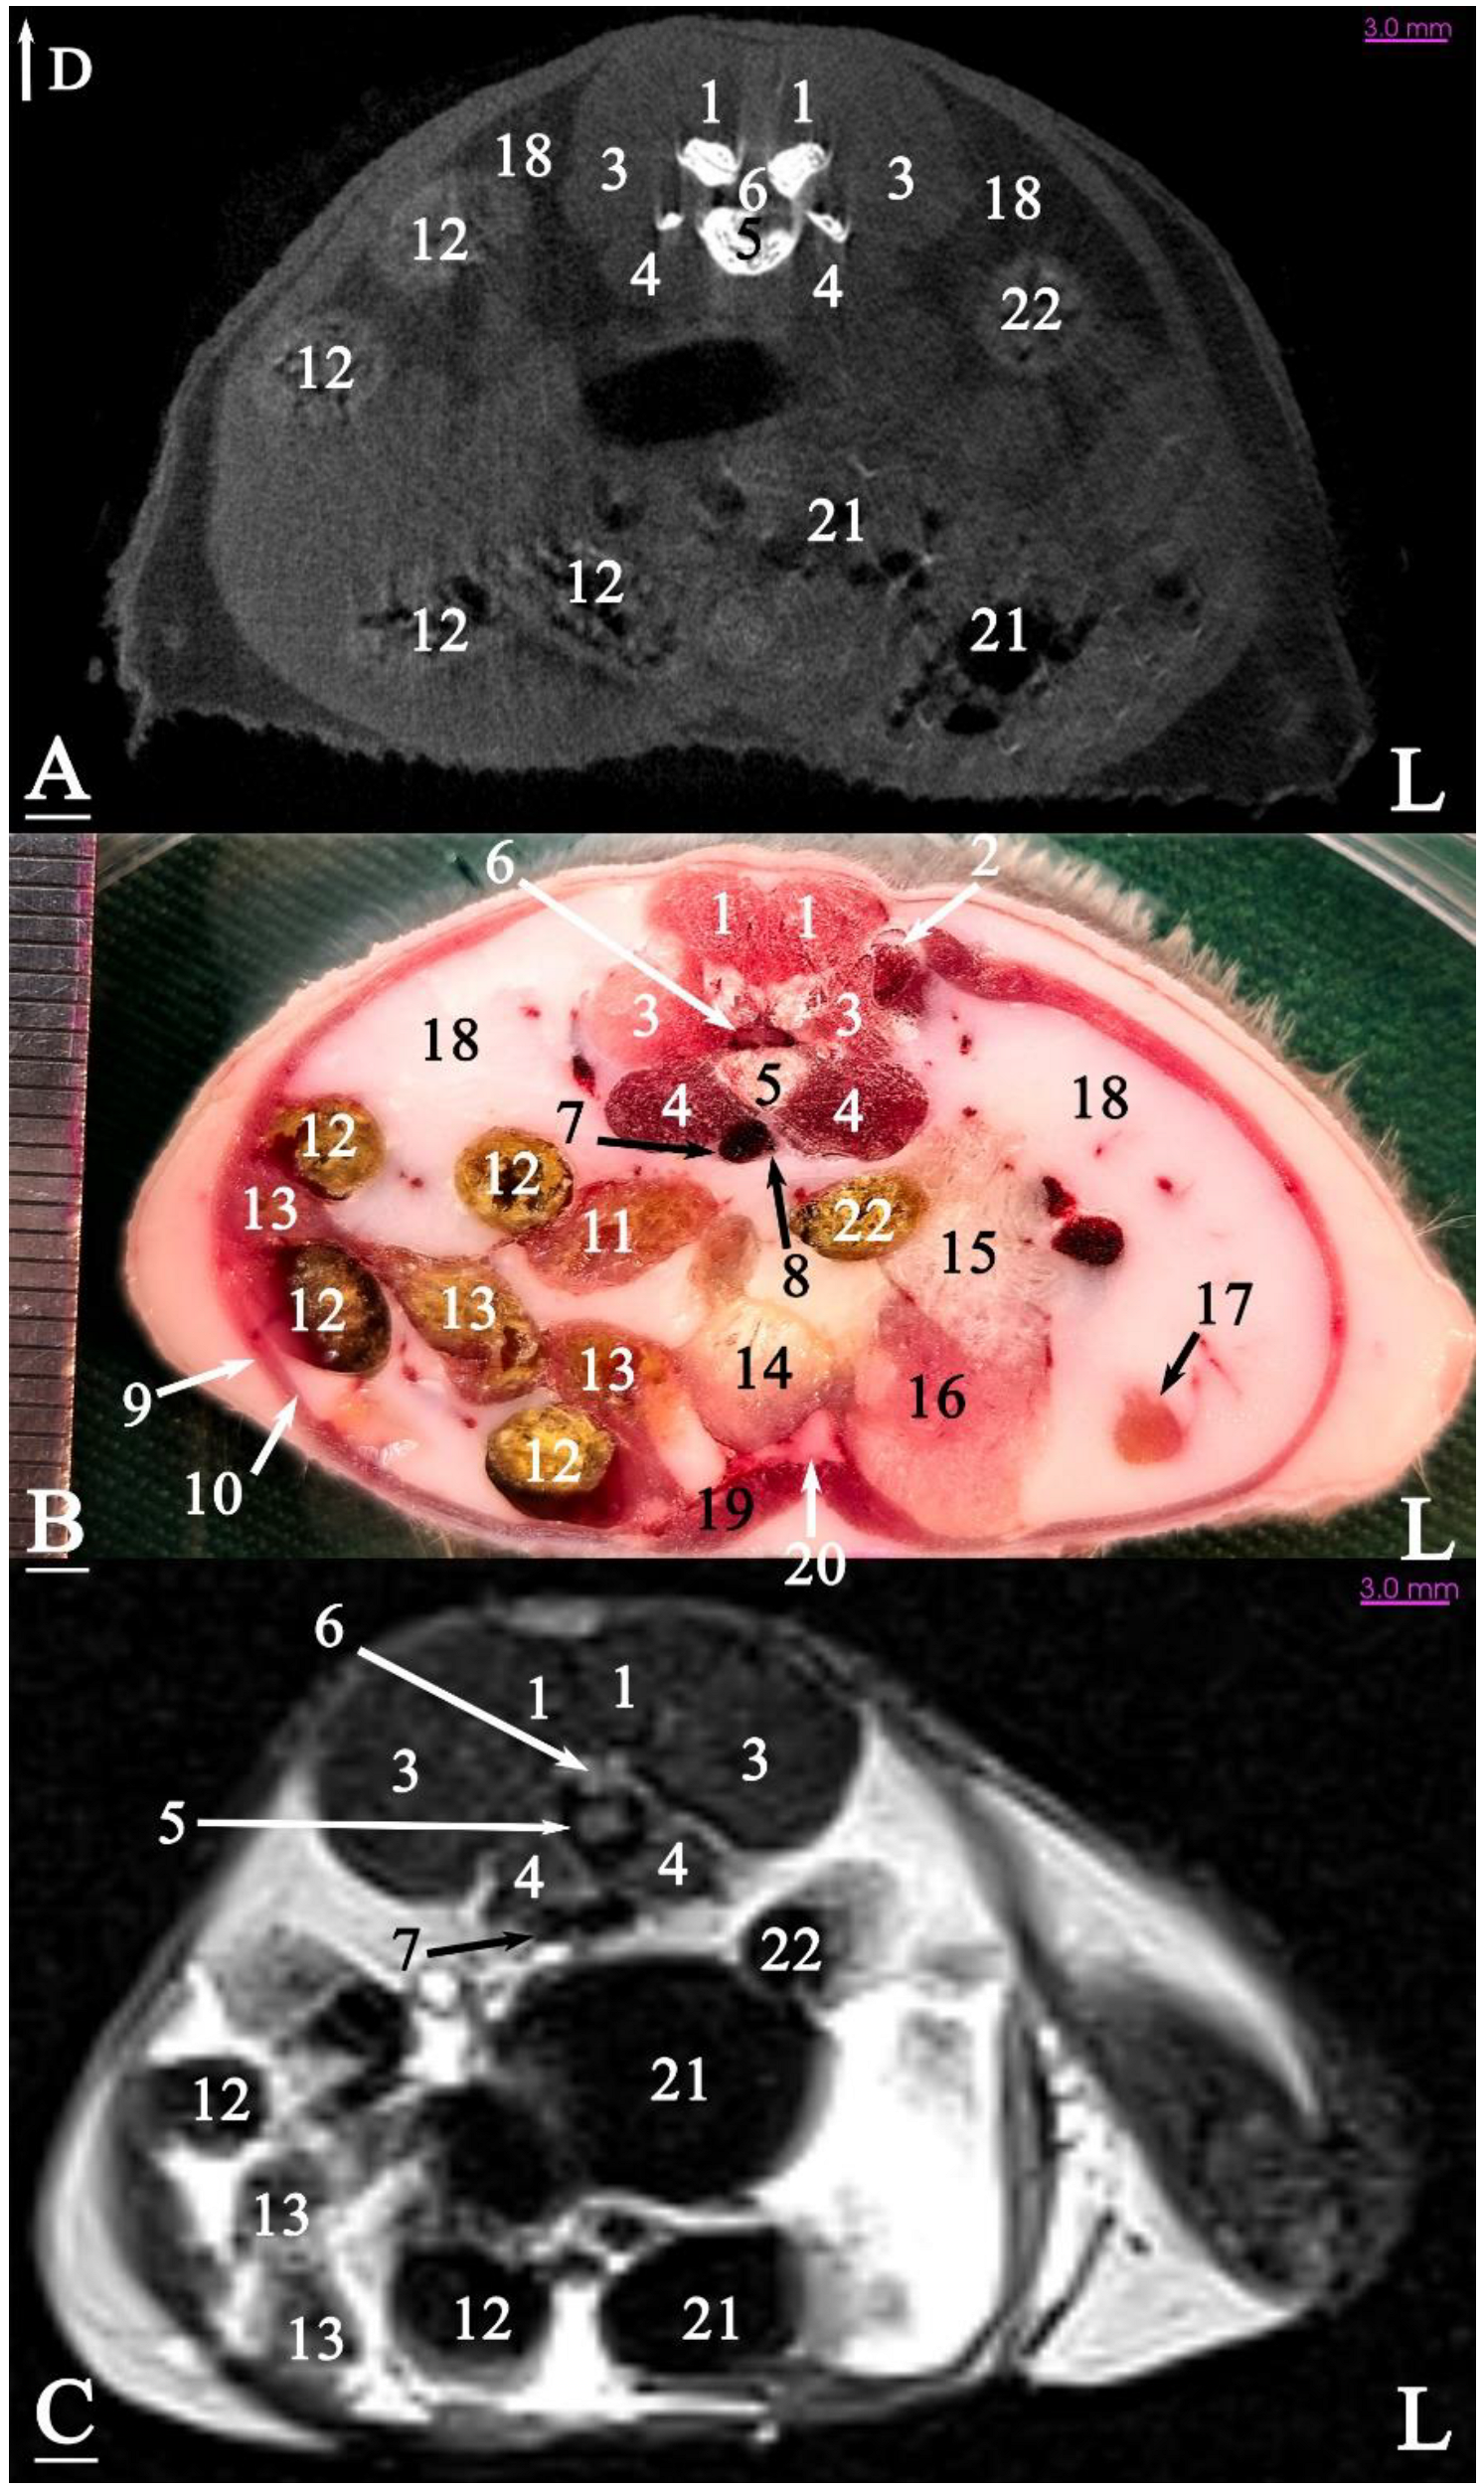

3.2.1. Transverse Cadaver Slices

3.3. Micro-CT Slices

3.4. MRI Slices